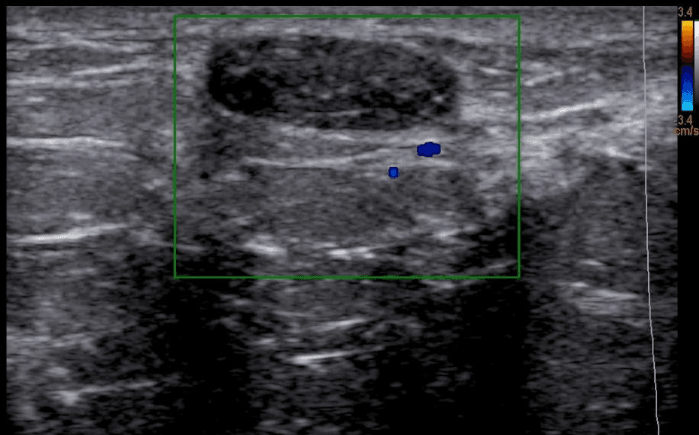

nódulo no ultrassom de mamas

Ultrassom de mamas demonstrando um nódulo provavelmente benigno. Na avaliação anatomopatológica foi confirmado fibroadenoma (nódulo benigno).